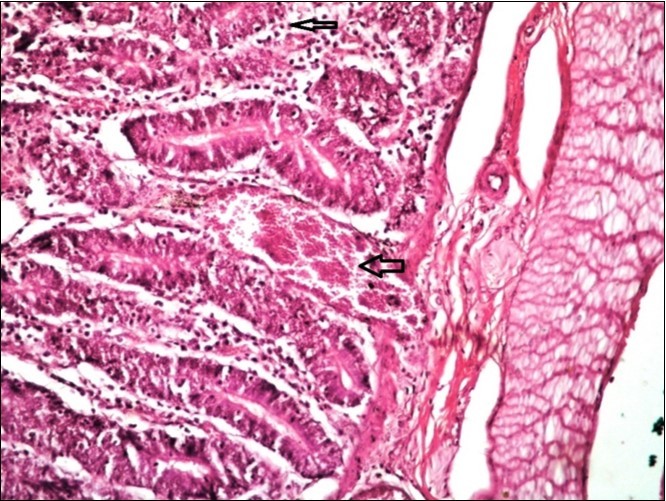

Figure 13.Small intestine (dead cattle less than 1 year old) showed hydropic degeneration, congested blood vessels, inflammatory cells (H&E, X 30).